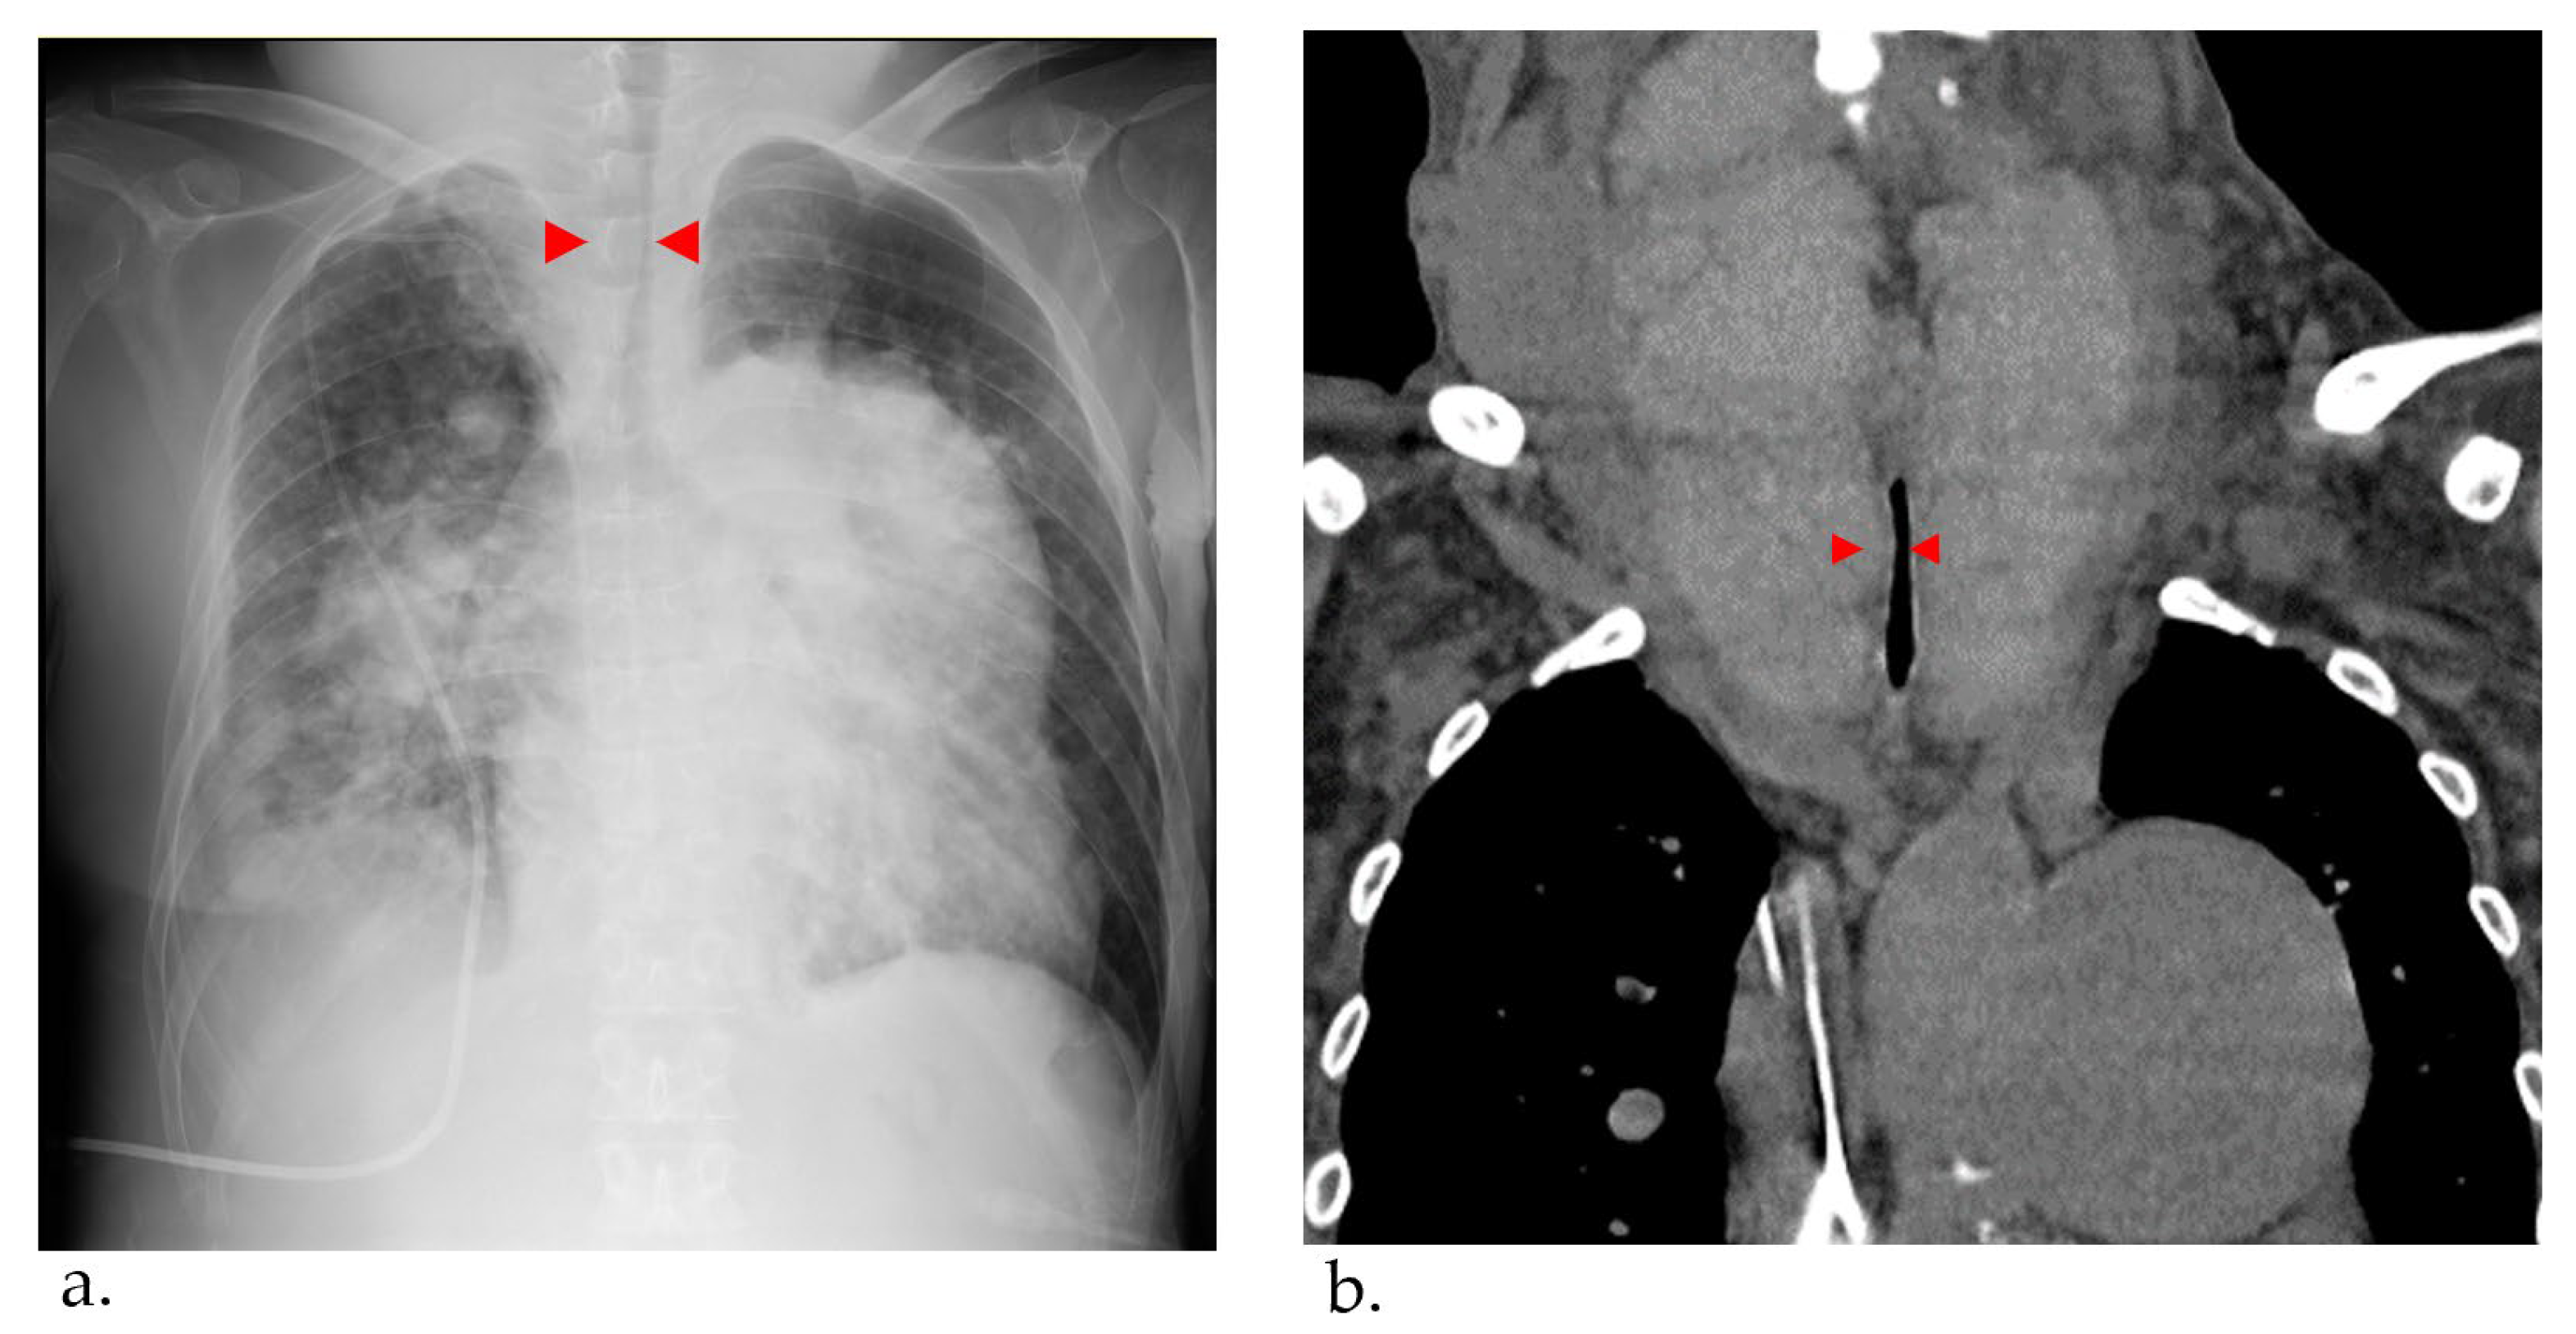

A Case of Giant Goiter Associated with Airway Stenosis Caused by Long-Term Intravenous Epoprostenol Therapy for Idiopathic Pulmonary Arterial Hypertension

2. Case Report